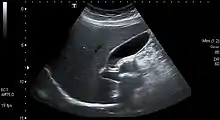

Abdominal ultrasonography showing gallbladder and common bile duct

The gallbladder varies in size, shape, and position among different people.[2] Rarely, two or even three gallbladders may coexist, either as separate bladders draining into the cystic duct, or sharing a common branch that drains into the cystic duct. Additionally, the gallbladder may fail to form at all. Gallbladders with two lobes separated by a septum may also exist. These abnormalities are not likely to affect function and are generally asymptomatic.[8]

The location of the gallbladder in relation to the liver may also vary, with documented variants including gallbladders found within,[9] above, on the left side of, behind, and detached or suspended from the liver. Such variants are very rare: from 1886 to 1998, only 110 cases of left-lying liver, or less than one per year, were reported in scientific literature.[10][11][2]